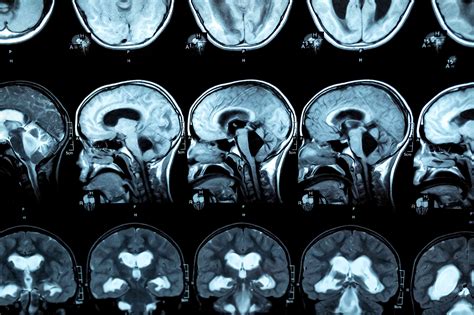

To confirm a diagnosis, physicians rely on a combination of clinical evaluation and advanced imaging technology. Because hydrocephalus in adults shares symptoms with conditions like Alzheimer’s or Parkinson’s, accurate diagnosis is the first priority.

MRI (Magnetic Resonance Imaging) Provides detailed images of the brain to visualize ventricle size.

CT Scan Quickly identifies enlarged ventricles and potential obstructions.